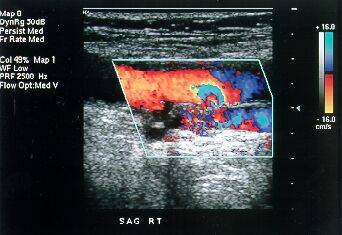

Color

Doppler |

Q1. What is Color Doppler?

A. Color Doppler is a special ultrasound

technique, which allows us to evaluate blood vessels.

Q2. What is the principle?

A. Using the Doppler principle of changing

pitch with velocity, ultrasound waves that reflect

from the red blood corpuscles in arteries and veins

are evaluated for velocity and amplitude and color

maps of the vessels can be generated.

Is special equipment required?

An ultrasound machine equipped with color Doppler

facilities is required. These are now readily available

at many centers.

Q3. What is its utility?

A. Color Doppler is very useful in evaluating

the carotid arteries in the neck, the heart (echocardiography),

the arteries and veins in the abdomen and the arteries

and veins in the upper and lower limbs.